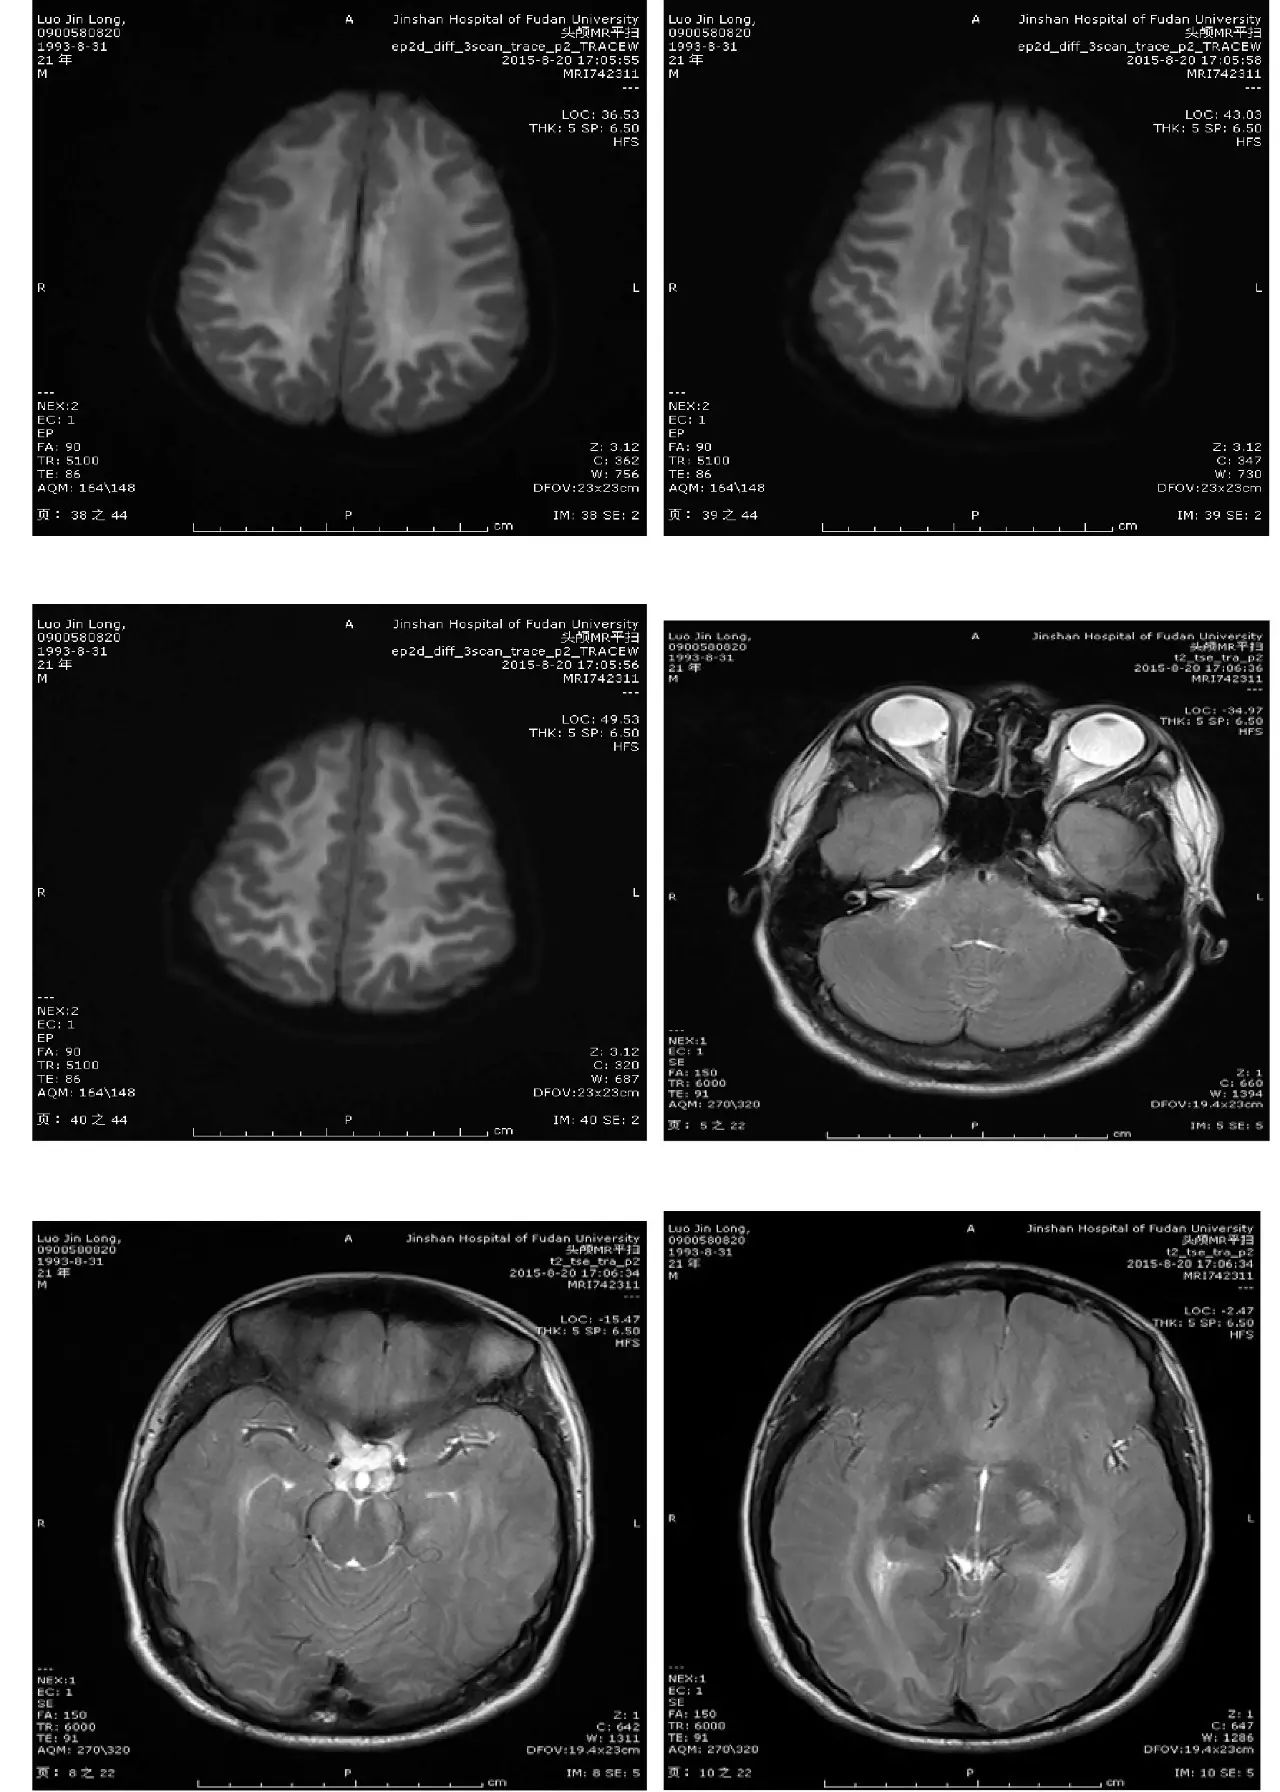

主诉:头痛、反应迟钝、口齿不清4天

现病史:头中线部位钝痛,反应迟钝,口齿不清,无发热,无恶心、呕吐,无饮水呛咳,四肢乏力。无麻木不适。2天后出现视物模糊。外院头颅CT:两侧大脑半球低密度灶。

(点击查看高清图)